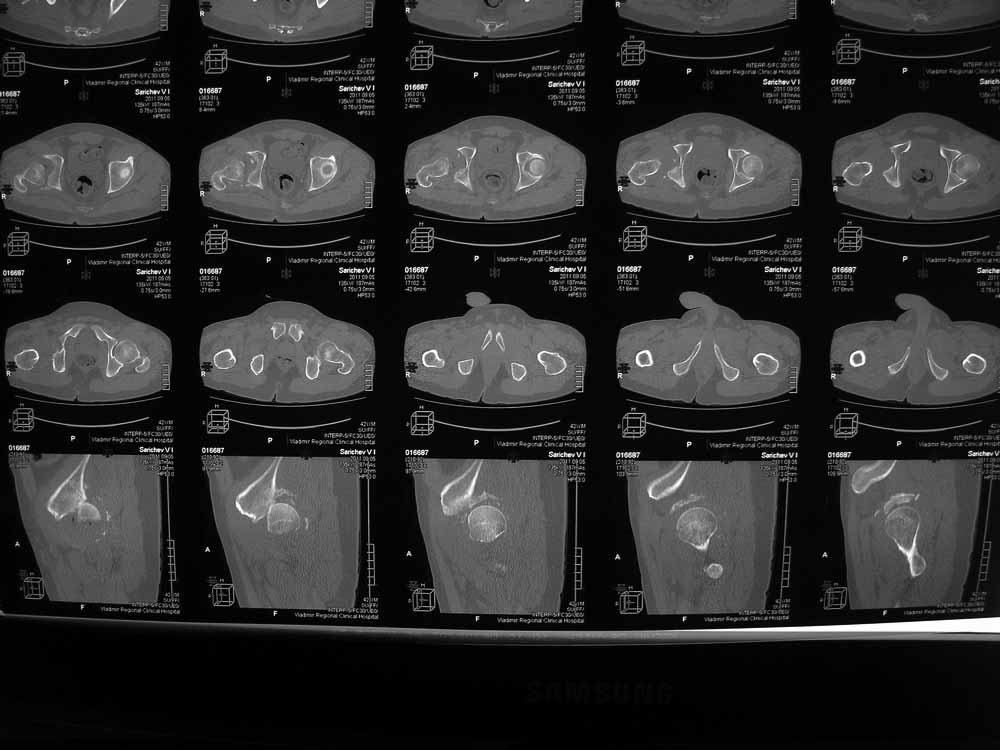

42 года, майор запаса. Травма от 20.06 - ДТП. Лечился в гражданском ЛПУ. Вывих бедра диагностирован только 4 недели спустя. "Тянулся", неоднократно - попытки закрытой репозиции. Попытка открытой репозиции - без результата. Потом опять пытались закрыто, сказали, что вправили, тянулся. После снятия ССВ - опять вывих. Поступил к нам. Сейчас - СРБ больше 10, в ОАК - воспаление. Местно - головка кзади и кверху, укорочение 7, голова подвижна. Отек, незначительная боль в в/3 бедра. Пассивно из наружной ротации выводится, активных движений в ноге нет. Рубец по наружной поверхности верхней трети бедра, без воспаления. Каким образом выполнялось открытое вправление - данных нет. Окончательно снят с вытяжения 2 недели назад.

Структуру головки не очень хорошо видно, есть перелом нижнего отдела головки БК, сломанный задний край небольшой. Срок после травмы 4 недели, молодой возраст. Есть смысл синтезировать ВВ, а дальше посмотреть. Будут проблемы - легче будет протез ставить, ну а если лет 8-10 сустав поработает, то и это хорошо. Если вы уж решили делать протезирование, не мудрите, вполне можно обойтись стандартной вертлужной впадиной с укреплением ее винтами.

Вот еще сканы.